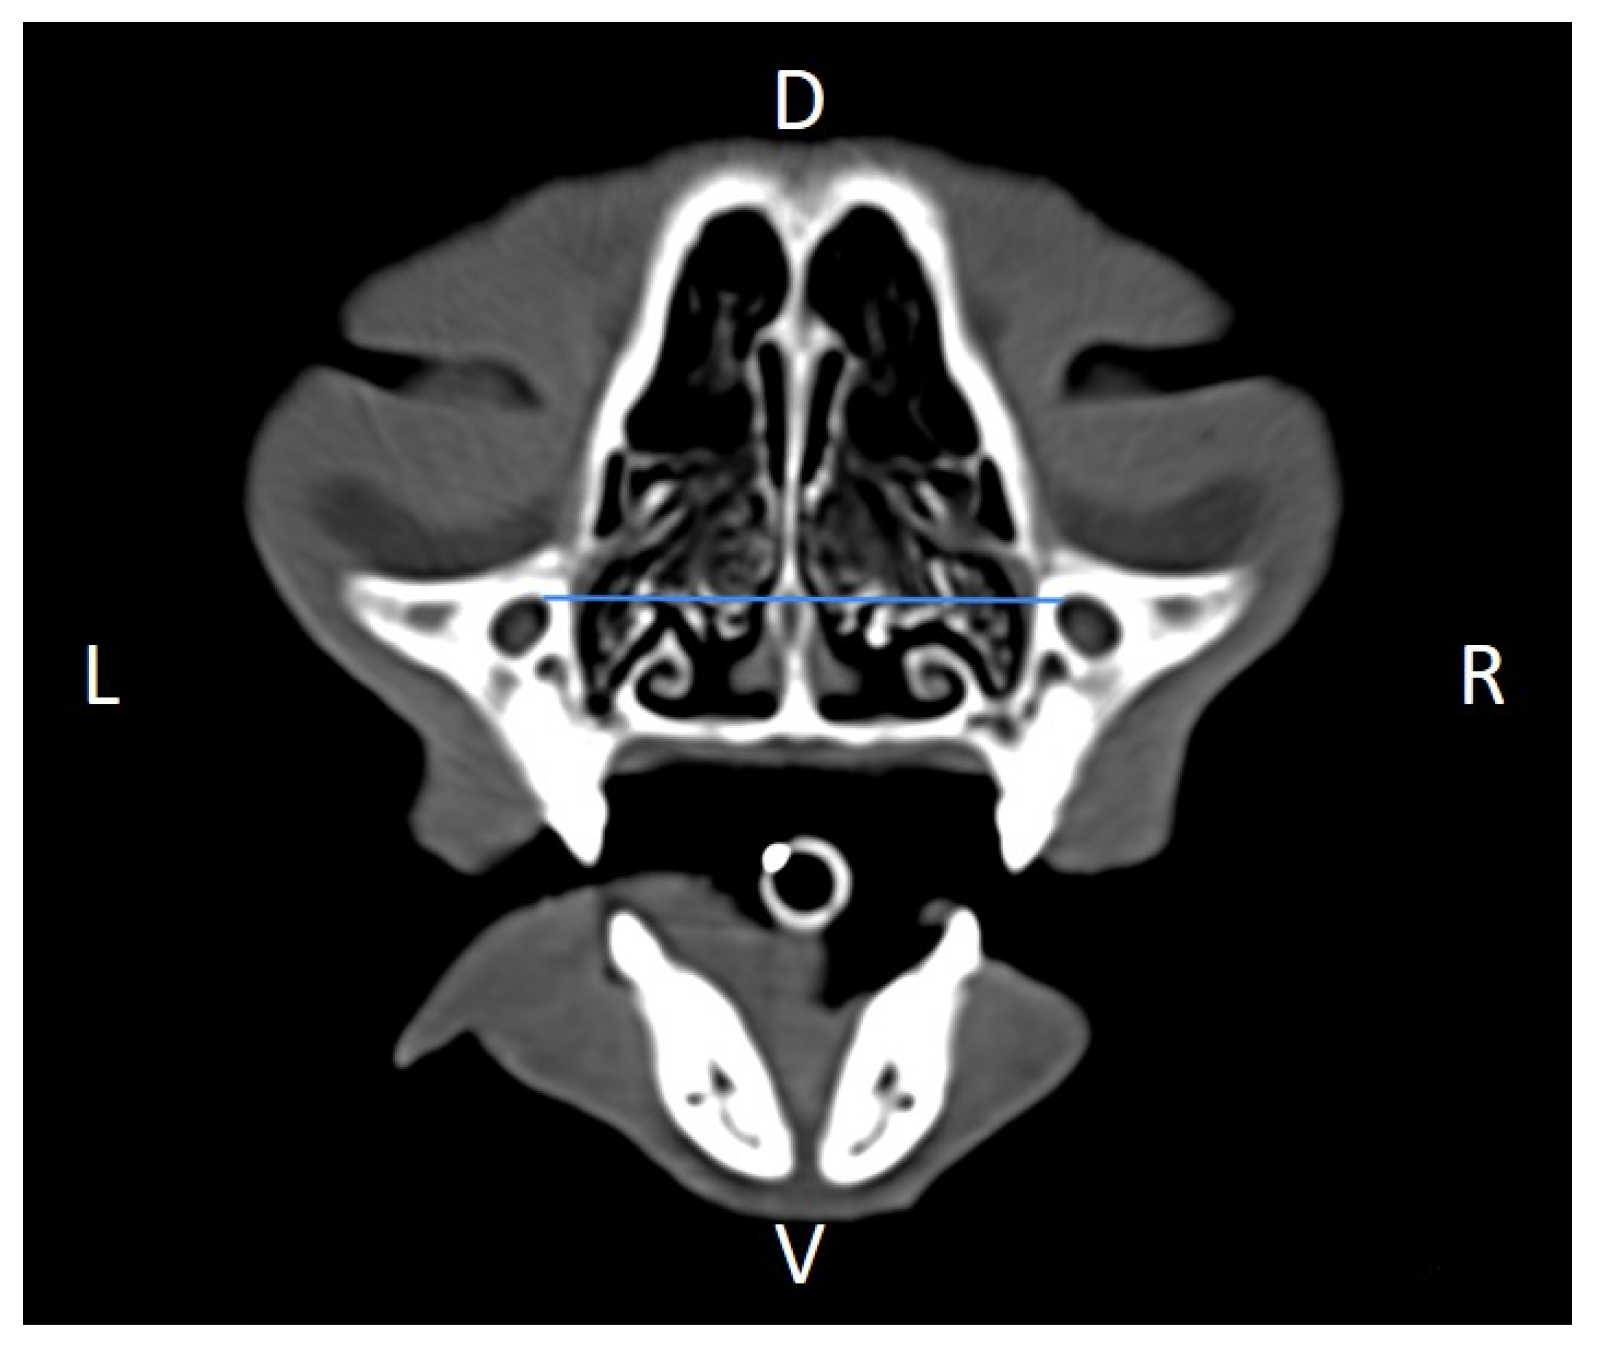

In order to perform the linear measurements described in Table 1, firstly, rotational misalignment of the head was corrected by aligning the images in the three planes, as demonstrated in Figure 1. The sagittal plane (Figure 1A) was aligned at the level of the nasal septum and the interincisive midline; the transverse plane (Figure 1B) was oriented perpendicular to the hard palate; and the dorsal plane (Figure 1C) was parallel to the hard palate. Since the computer program used allowed for the simultaneous visualization of the three anatomical planes (sagittal, transverse, and dorsal), the identification of the measurement planes and the delimitation of the anatomical structures to be measured was performed with greater precision.

Figure 1. Representative multiplanar computed tomography reconstruction showing the sagittal (A), transverse (B), and dorsal (C) planes. The sagittal plane was aligned at the level of the nasal septum and the interincisive midline; the transverse plane was oriented perpendicular to the hard palate; and the dorsal plane was parallel to the hard palate. D, dorsal, L, left, R, right, Ro, rostral, V, ventral.